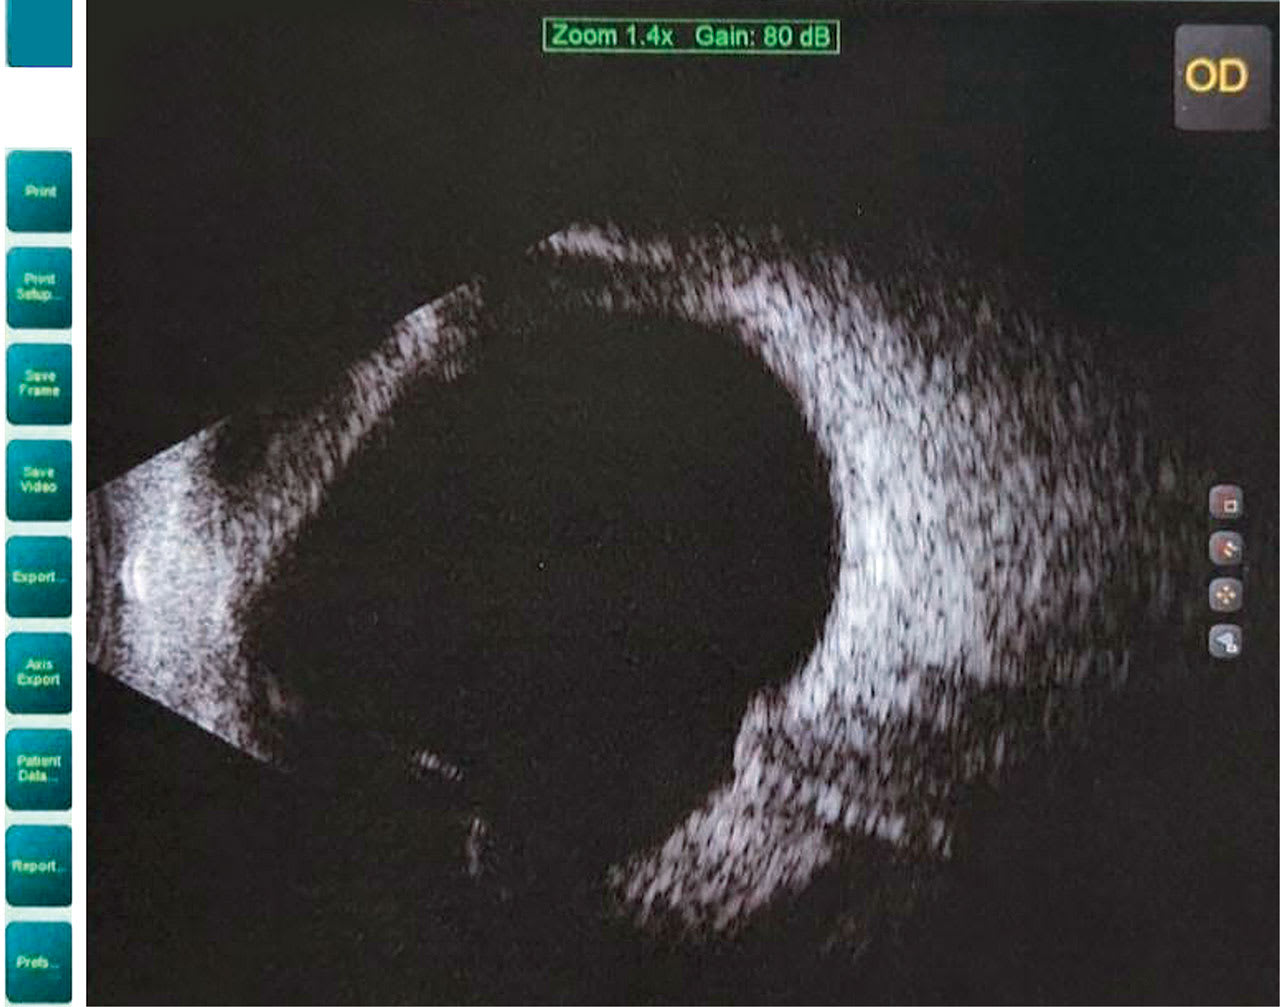

His BCVA in spectacles was 20/20 bilaterally. The external examination was unremarkable. Intraocular pressure was 13 mmHg in both eyes. The lids and lashes were of normal appearance. The cornea exhibited symmetric 360º thinning of the limbus. The posterior segment was remarkable for bilateral optic disc drusen (Figure 2).

The corneal topography maps are shown in Figure 3. The patient was diagnosed with megalocornea, a rare, typically bilateral condition with corneal diameter greater than 13mm. There is no corneal edema, scarring, or buphthalmos in patients who have megalocornea. It is typically inherited as an X-linked genetic pattern and can be associated with Alport Syndrome, Marfan syndrome, Ehlers-Danlos syndrome, and Down syndrome.10 Scleral, corneal GP, and soft contact lens options were discussed with the patient.